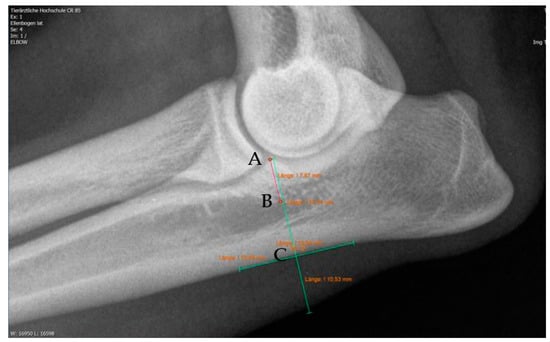

Moreover, Trochlear Notch Sclerosis (TNS), a radiological term denoting increased bone radio-opacity in the ulnar trochlear notch region, was quantified. The measurements adhered to the methodology outlined by Draffan et al. [

13], and the comprehensive TNS ratio of sclerosis to the ulnar depth was subsequently computed (

Figure 1). All measurements were performed by the first author of the article.